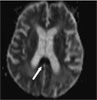

MRI scans of the head revealed acute infarcts (arrows) in the right corona radiata, right centrum semiovale, and anterior and posterior corpus callosum.

In this patient, the syndrome manifested by her left hand can be attributed to the posterior callosal infarct, while the grasping nature of her dominant right “alien” hand may result from a new anterior callosal infarct combined with the prior parietal lobe infarct. Despite the association of this syndrome with Alzheimer- type dementia, we believe our patient's condition was related to the new infarcts.